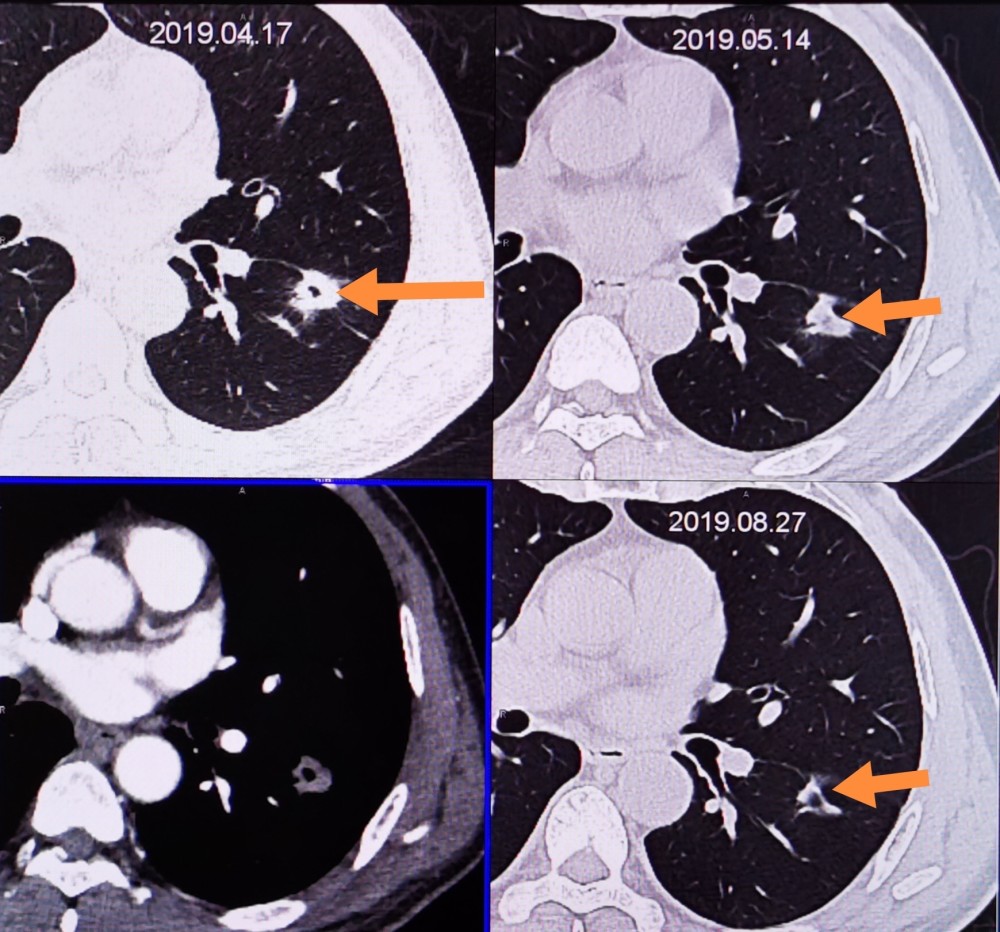

ct50211:两肺弥漫性小结节,进行性增多,如何诊断